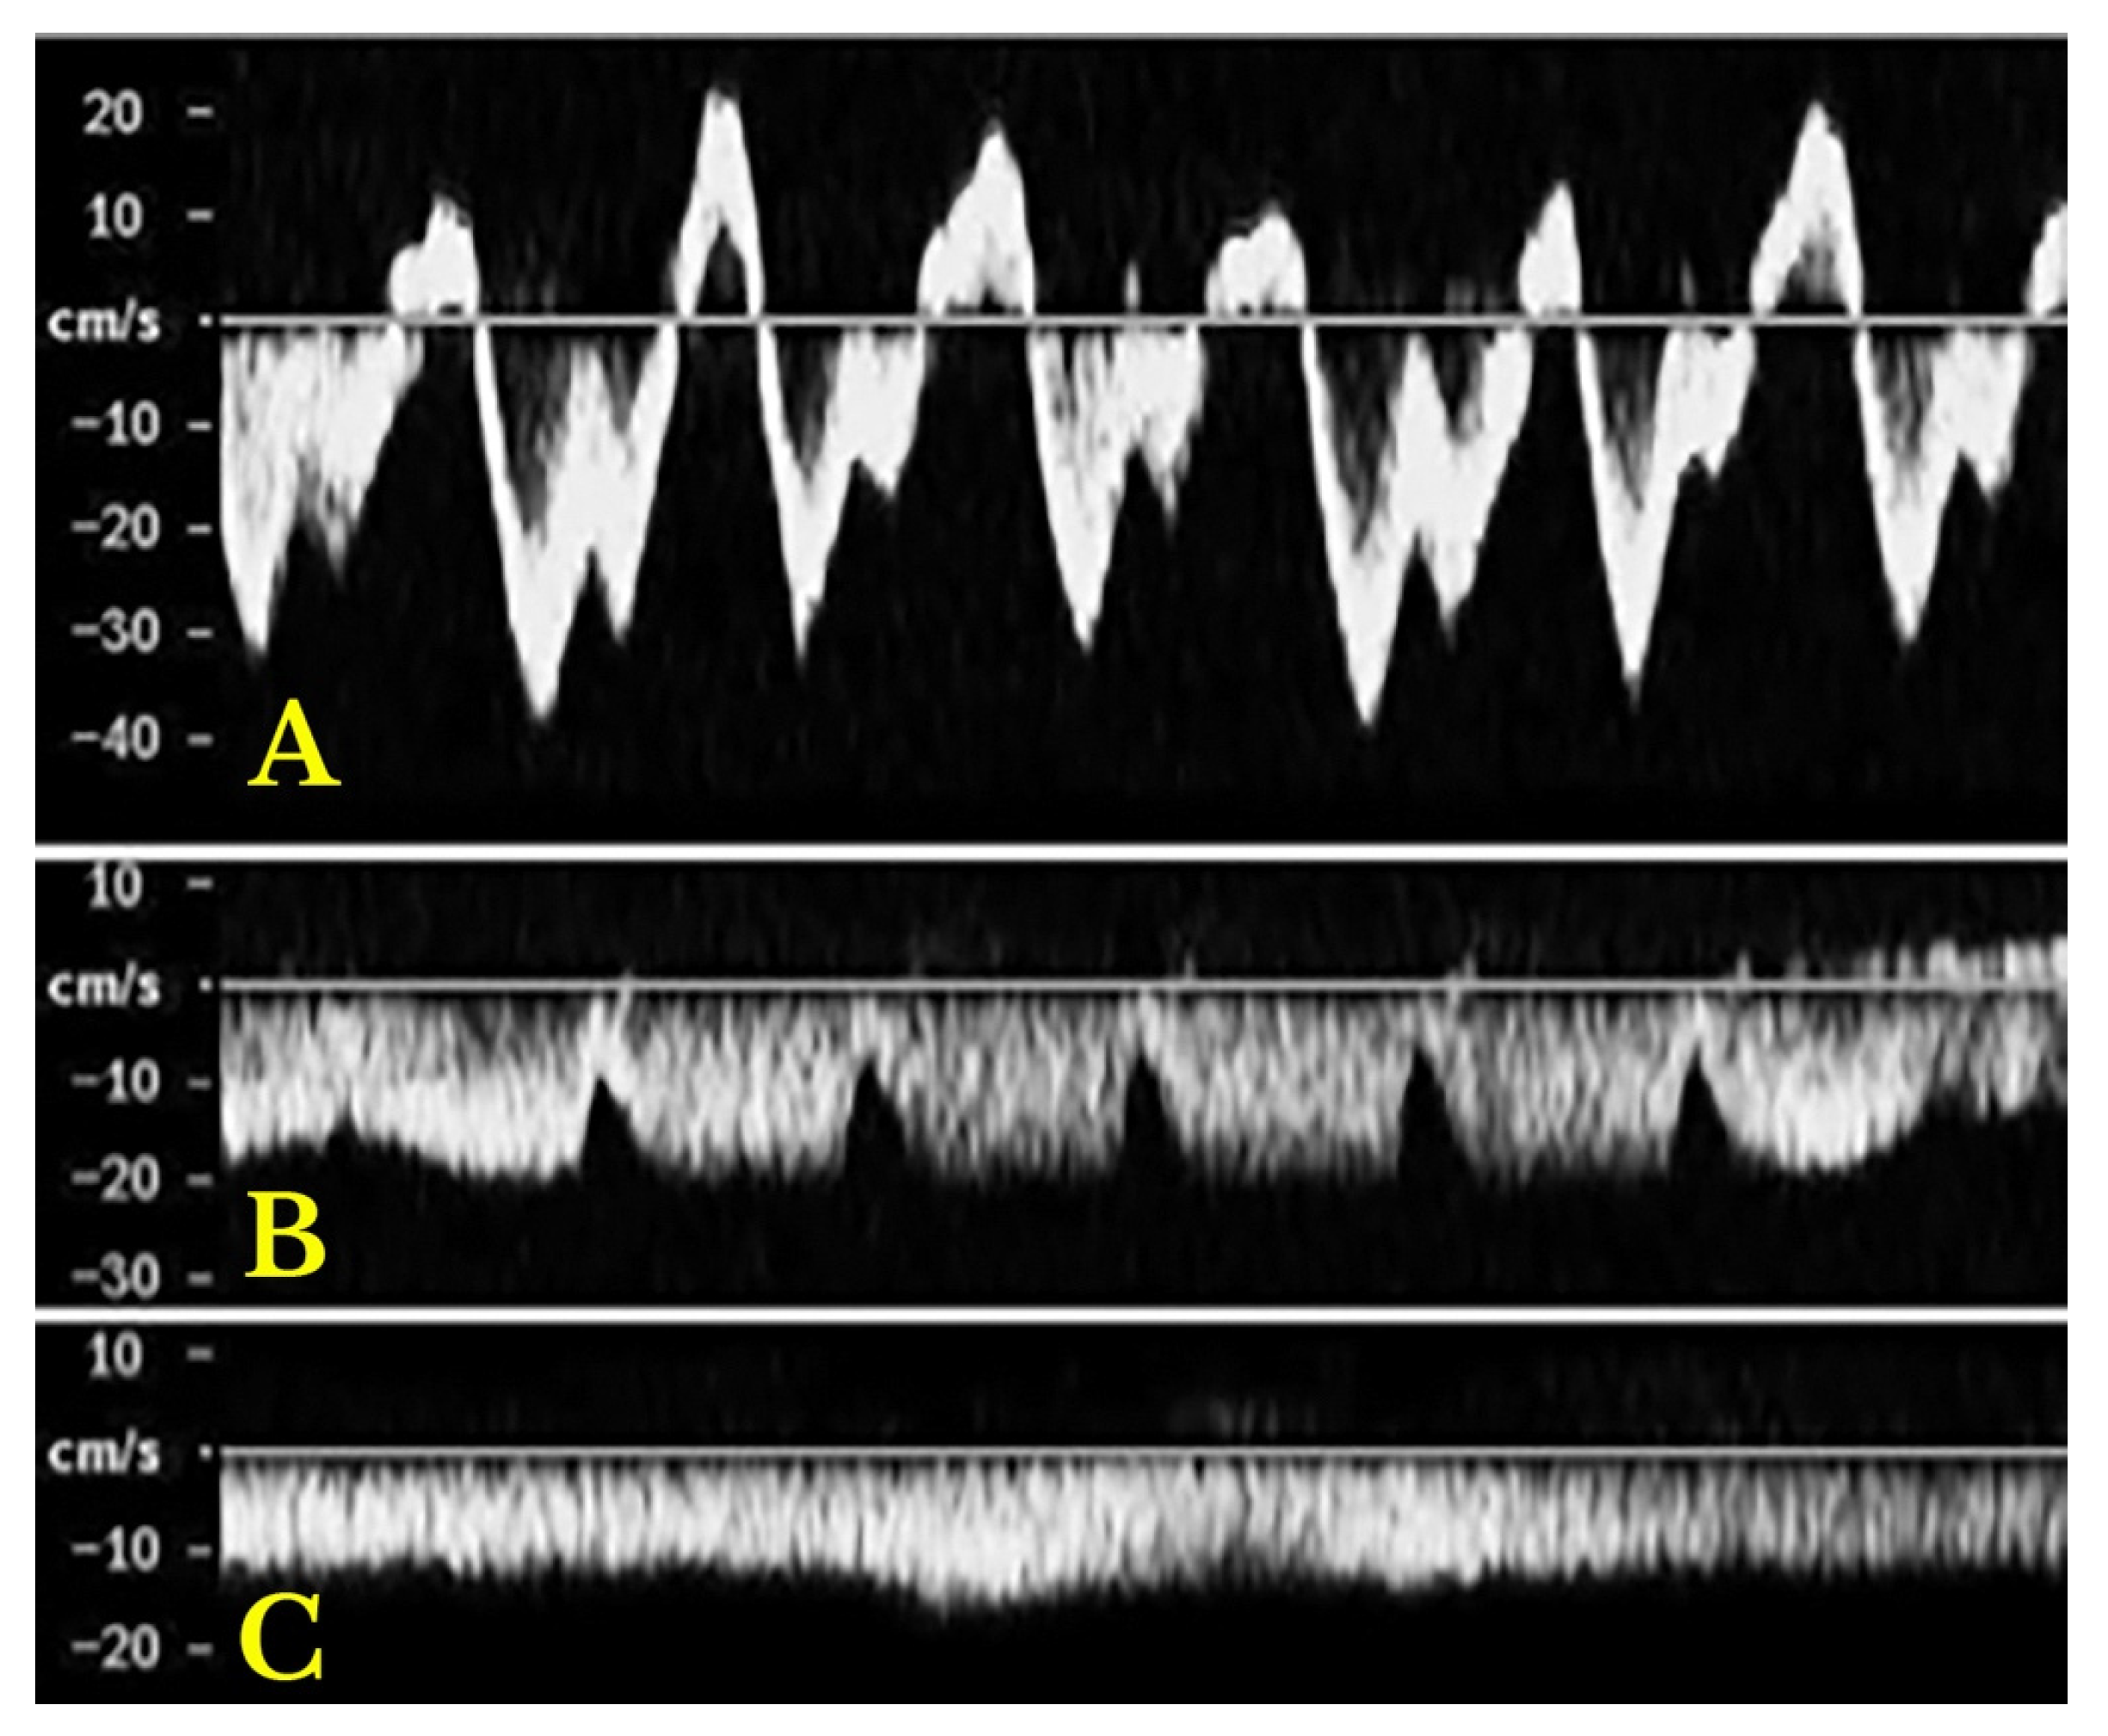

- Increased Pulsatility (Pulsatile Waveform): A pulsatile portal venous flow occurs when there is a significant difference between peak systolic and end-diastolic velocities. This is due to abnormal transmission of pressure through the hepatic sinusoids, often caused by conditions like tricuspid regurgitation, right-sided heart failure (CHF), or arteriovenous shunting (as seen in cirrhosis or hereditary haemorrhagic telangiectasia (Figure 9A) [105]. Pulsatility can be differentiated clinically, with right-sided CHF and tricuspid regurgitation identifiable through the hepatic venous waveform and grayscale US showing dilated hepatic veins, unlike in cirrhosis, where hepatic veins are compressed.

- Slow Portal Venous Flow: Slow flow occurs when back pressure restricts forward flow, typically indicating portal hypertension. In these cases, peak velocity is less than 16 cm/s [106]. Causes of portal hypertension include cirrhosis, portal vein thrombosis (prehepatic), and right-sided heart failure (posthepatic). The most specific findings include the development of portosystemic shunts (like a recanalized umbilical vein) and slow or reversed (hepatofugal) flow.

- Hepatofugal (Retrograde) Flow: Hepatofugal flow happens when the pressure in the portal vein exceeds that of the liver, causing flow to reverse and appear below the baseline. This is another indicator of portal hypertension, which can be caused by various conditions, including cirrhosis, right-sided heart failure and other portal vein obstructions [107] (Figure 9).Figure 9. (A) Increased pulsatility due to arteriovenous shunting in a case of hereditary haemorrhagic telangiectasia; (B) Reduced Portal Flow in a case of cirrhosis (C) Hepatofugal Flow of Portal Vein is a late sign of Portal Hypertension. It happens when the pressure in the portal vein exceeds that of the liver, causing flow to reverse and appear below the baseline. This is another indicator of portal hypertension, which can be caused by various conditions, including cirrhosis, right-sided heart failure and other portal vein obstructions.Figure 9. (A) Increased pulsatility due to arteriovenous shunting in a case of hereditary haemorrhagic telangiectasia; (B) Reduced Portal Flow in a case of cirrhosis (C) Hepatofugal Flow of Portal Vein is a late sign of Portal Hypertension. It happens when the pressure in the portal vein exceeds that of the liver, causing flow to reverse and appear below the baseline. This is another indicator of portal hypertension, which can be caused by various conditions, including cirrhosis, right-sided heart failure and other portal vein obstructions.